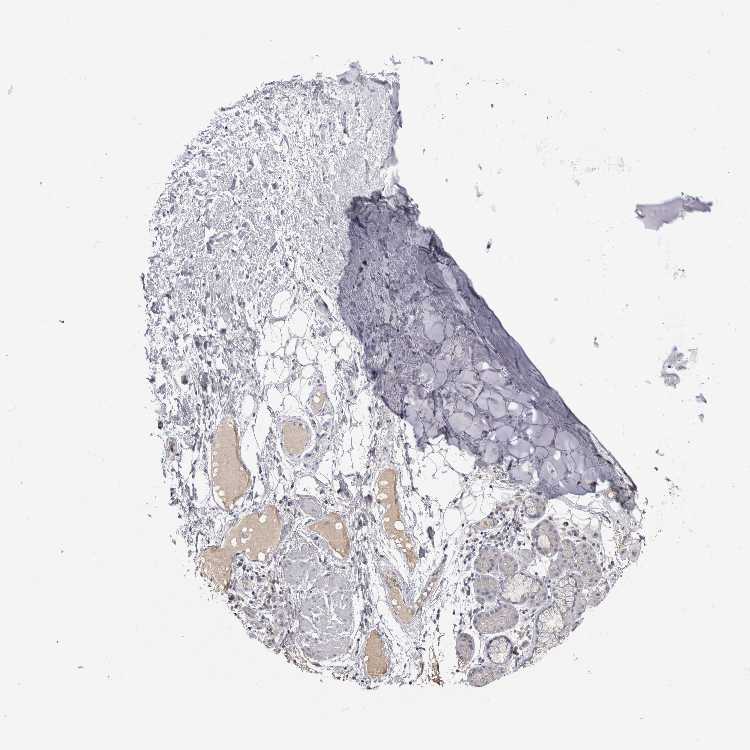

SOFT TISSUE 1 - Antibody stainingi

Antibody staining in the annotated cell types in the current human tissue is reported as not detected, low, medium, or high, based on conventional immunohistochemistry profiling in selected tissues. This score is based on the combination of the staining intensity and fraction of stained cells.

Each image is clickable and will lead to virtual microscopy that enables deeper exploration of all samples and also displays staining intensity scores, fraction scores and subcellular localization as well as patient and tissue information for each sample.

Antibody HPA045549Antibody HPA045579Antibody CAB025138

Chondrocytes --Not detected

Fibroblasts Not detectedNot detectedNot detected

Peripheral nerve Not detectedNot detectedNot detected